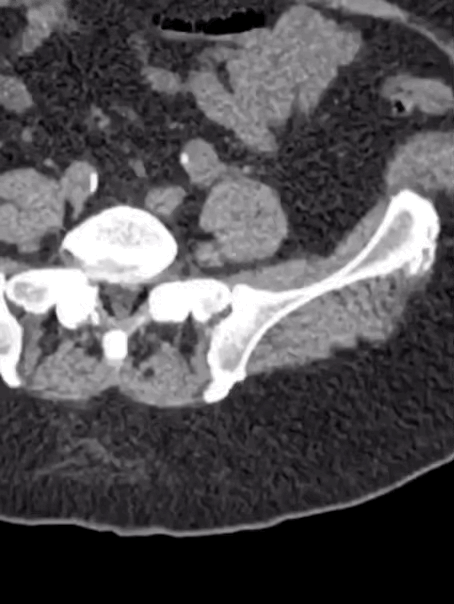

Case 6

A male in his 30s presents with abdominal pain. Here is a non contrast CT of his abdomen and pelvis.

Tap the first icon on the left to scroll.

What best describes the main scan finding? Choose one from the following options: